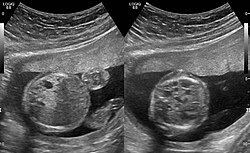

CPAMs are often identified during routine prenatal ultrasonography. Identifying characteristics on the sonogram include: an echogenic (bright) mass appearing in the chest of the fetus, displacement of the heart from its normal position, a flat or everted (pushed downward) diaphragm, or the absence of visible lung tissue.

CPAMs are classified into three different types based largely on their gross appearance. Type I has a large (>2 cm) multiloculated cysts. Type II has smaller uniform cysts. Type III is not grossly cystic, referred to as the "adenomatoid" type. Microscopically, the lesions are not true cysts, but communicate with the surrounding parenchyma. Some lesions have an abnormal connection to a blood vessel from an aorta and are referred to as "hybrid lesions."

The earliest point at which a CPAM can be detected is by prenatal ultrasound. The classic description is of an echogenic lung mass that gradually disappears over subsequent ultrasounds. The disappearance is due to the malformation becoming filled with fluid over the course of the gestation, allowing the ultrasound waves to penetrate it more easily and rendering it invisible on sonographic imaging. When a CPAM is rapidly growing, either solid or with a dominant cyst, they have a higher incidence of developing venous outflow obstruction, cardiac failure and ultimately hydrops fetalis. If hydrops is not present, the fetus has a 95% chance of survival. When hydrops is present, risk of fetal demise is much greater without in utero surgery to correct the pathophysiology. The greatest period of growth is during the end of the second trimester, between 20–26 weeks.

A measure of mass volume divided by head circumference, termed cystic adenomatoid malformation volume ratio (CVR) has been developed to predict the risk of hydrops. The lung mass volume is determined using the formula (length × width × anteroposterior diameter ÷ 2), divided by head circumference. With a CVR greater than 1.6 being considered high risk. Fetuses with a CVR less than 1.6 and without a dominant cyst have less than a 3% risk of hydrops. After delivery, if the patient is symptomatic, resection is mandated. If the infant is asymptomatic, the need for resection is a subject of debate, though it is usually recommended. Development of recurrent infections, rhabdomyosarcoma, adenocarcinomas in situ within the lung malformation have been reported.[6]